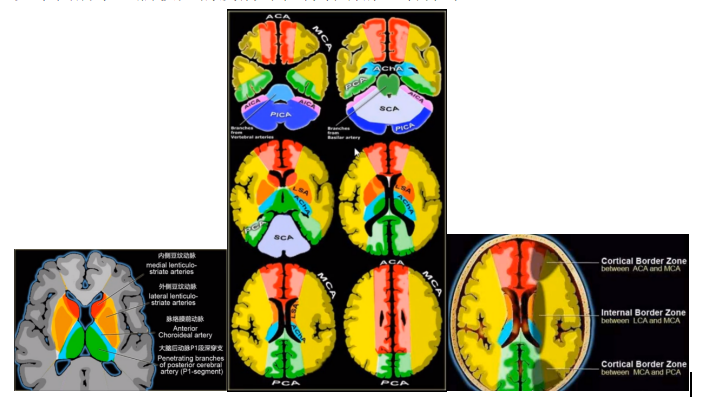

如下图所示,脑梗死的发病部位符合动脉血管分布区:

1.脑梗死影像学表现及分期

(1)超急性期(<6h):CT 及 MRI 检查阴性,DWI 呈明显高信号。

(2)急性期(6-72h):CT 表现低密度区,MR 表现长 T1 长 T2 异常信号,DWI 呈较明显高信号。

(3)亚急性期(72h-10d):CT 表现同时累及灰白质的楔形或三角形低密度区,MR 可伴出血, DWI 呈明显高信号,占位效应显著,增强扫描可见强化。

(4)慢性期(&11d):脑软化,脑萎缩。